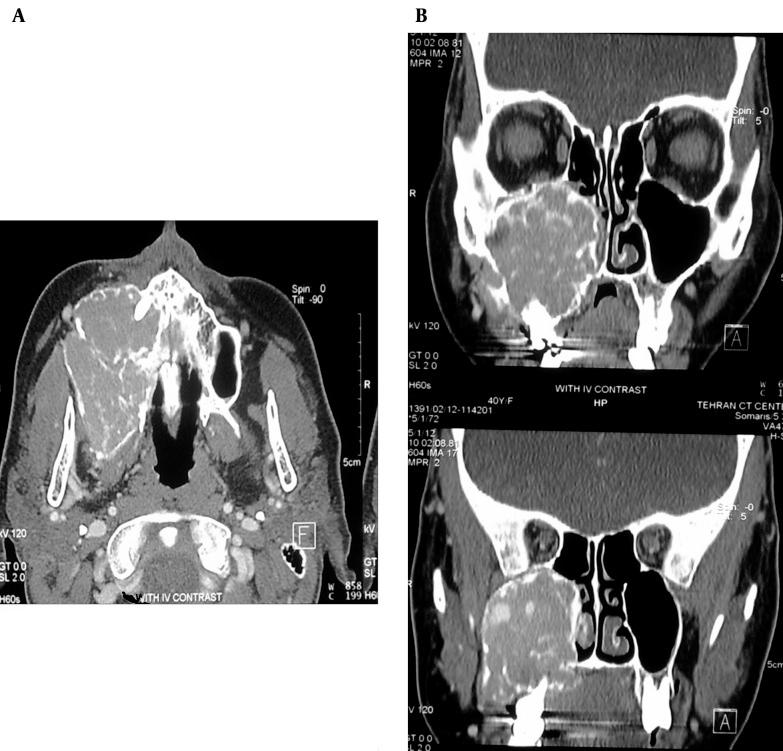

Primary hyperparathyroidism is an endocrine disorder recognized by hyperfunction of parathyroid gland, which can result in persistent bone absorption and brown tumor. Facial involvement of brown tumor is rare and usually involves the mandible. Giant cell tumor ( GCT) is an expansile osteolytic bone tumor which is very similar in clinical, radiological and histological features to brown tumor. Herein, we present a 35-year-old woman with an 11-month history of gradually swelling of the right maxilla and buccal spaces began during pregnancy two years ago. No other clinical or laboratory problems were detected. Postpartum CT scan demonstrated a lytic expansile multi-septated mass lesion containing enhancing areas, which initially described as GCT of the right maxillary sinus following surgery. Four months later, gradual progressive swelling of the bed of tumor was recurred and revised pathological slices were compatible with GCT. Regarding patient recent paresthesia, repeated laboratory tests were performed. Finally, according to laboratory results (elevation of serum calcium and parathyroid hormone), ultrasonographic findings and radioisotope scan (Sestamibi), probable parathyroid mass and brown tumor of maxilla was diagnosed. Pathology confirmed hyperplasia of right inferior parathyroid gland. Our case was thought-provoking due to its interesting clinical presentation and unusual presentation of brown tumor in parathyroid hyperplasia.

原发性甲状旁腺功能亢进是一种因甲状旁腺功能亢进而被识别的内分泌疾病,可导致持续性骨质吸收和棕色瘤。棕色瘤累及面部较为罕见,通常累及下颌骨。骨巨细胞瘤(GCT)是一种膨胀性溶骨性骨肿瘤,在临床、影像学和组织学特征上与棕色瘤非常相似。在此,我们报告一名35岁女性,自两年前怀孕期间开始出现右上颌骨和颊间隙逐渐肿胀,病程11个月。未发现其他临床或实验室问题。产后CT扫描显示一个溶骨性膨胀性多房性肿块病变,内有强化区域,术后最初诊断为右上颌窦骨巨细胞瘤。四个月后,肿瘤床逐渐进行性肿胀复发,再次病理切片符合骨巨细胞瘤。鉴于患者近期出现感觉异常,进行了多次实验室检查。最后,根据实验室检查结果(血清钙和甲状旁腺激素升高)、超声检查结果和放射性核素扫描(锝[99mTc]甲氧基异丁基异腈),诊断为可能的甲状旁腺肿块和上颌骨棕色瘤。病理证实右下甲状旁腺增生。我们的病例因其有趣的临床表现以及甲状旁腺增生中棕色瘤的不寻常表现而发人深省。